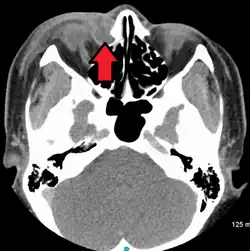

A case of dacryocystitis as seen on CT scan | |

Dacryocystitis is an infection of the lacrimal sac, secondary to obstruction of the nasolacrimal duct at the junction of the lacrimal sac.[1] The term derives from Greek dákryon 'tear' cysta 'sac' and -itis 'inflammation'.[2] It causes pain, redness, and swelling over the inner aspect of the lower eyelid and epiphora. When nasolacrimal duct obstruction is secondary to a congenital barrier it is referred to as dacryocystocele. It is most commonly caused by Staphylococcus aureus and Streptococcus pneumoniae.[3] The most common complication is corneal ulceration, frequently in association with S. pneumoniae.[3] The mainstays of treatment are oral antibiotics, warm compresses, and relief of nasolacrimal duct obstruction by dacryocystorhinostomy.[3]